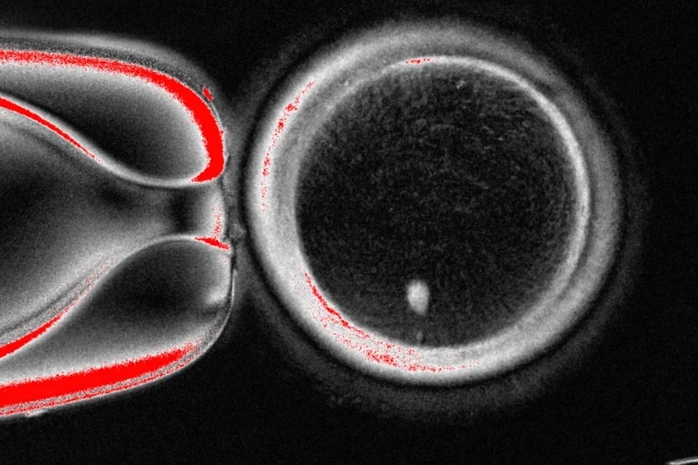

Hình ảnh dưới kính hiển vi của một trứng người có chứa nhân được lấy từ tế bào da. Ảnh do Phòng Thí nghiệm Mitalipov tại ĐH Y tế và Khoa học Oregon (Mỹ) cung cấp Ảnh: AP

Đây là bước tiến trong nỗ lực phát triển trứng hoặc tinh trùng nuôi cấy trong phòng thí nghiệm, nhằm một ngày nào đó có thể giúp con người thụ thai.Cụ thể, nhóm nghiên cứu tại Đại học Y tế và Khoa học Oregon đã loại bỏ nhân ra khỏi tế bào trứng người, rồi thay thế bằng nhân từ tế bào da.

Thế nhưng, tế bào da có đến hai bộ nhiễm sắc thể trong khi trứng và tinh trùng lẽ ra mỗi loại chỉ có một bộ để kết hợp lại trong quá trình thụ tinh. Vì vậy, các nhà nghiên cứu đã kích thích những tế bào giống trứng này loại bỏ bớt nhiễm sắc thể thừa, sau đó tiêm tinh trùng từ người hiến tặng vào và thúc đẩy tiến trình phát triển sau thụ tinh.